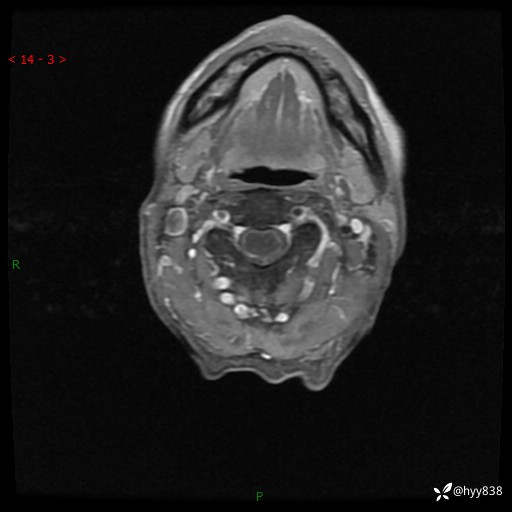

颈椎MRI平扫(sag T1WI+T2WI-fs+axi T2WI)

CE